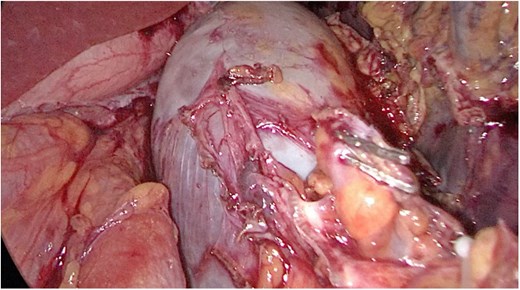

Multidisciplinary discussion was held to evaluate the most appropriate course of action for the patent condition, and the consensus was reached to pursue embolization as a first intervention. Embolization was performed by interventional radiology with no complications post-procedure, and the patient was optimized prior to her procedure. Patient was taken to the operating room in stable conditions. The spleen was enlarged around 20 cm. Inferiorly, the omentum and part of the transverse colon was attached to the spleen (Fig. 3), so we freed the omentum from the splenic tissue. The dissection continued until reaching short gastric vessels and entering the lesser sac (Fig. 4). Once the lesser sac was entered, the splenic vessels were identified (Figs 5 and 6), the splenic vein was hugely dilated with multiple collateral branching vessels at the hilum. Gaining posterior mobilization of the vein was challenging. The splenic artery was tortuous from the insertion around itself (Fig. 7). After complete mobilization of the fundus, we elected to divide each vessel starting with the splenic artery so we can achieve full mobilization of the vein (Fig. 9). After controlling the splenic artery, the splenic vein was dissected proximal to the splenic hilum (Fig. 8). It was hugely dilated and its wall is thickened secondary to AV fistula. It was difficult to achieve circumferential dissection, so we decided at that moment to convert to laparotomy to complete ligating the vein and to retrieve the specimen (Fig. 10a and b).

Anterior portion of the splenic vein seen posterior to the stomach.